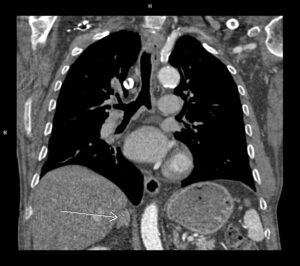

Figura 1: reconstrucţie aortă toracică

Discuţie caz nr 86: Valva aortică este morfologic bicuspidă la 1% din populație și asociază, cu timpul, creștere de calibru a aortei ascendente datorită fluxului turbulent determinat de modificarea de morfologie a valvei aortice – în unele cazuri această malformație congenitală asociază modificare de calibru a aortei descendente proximal – coarctaţie de aortă.

La acest pacient se remarcă și faptul că în jumătatea proximală a arterei subclavii stângi este prezentă o placă necalcificată dezvoltată circumferential ce produce stenoza severă – reducere de lumen de 80%.